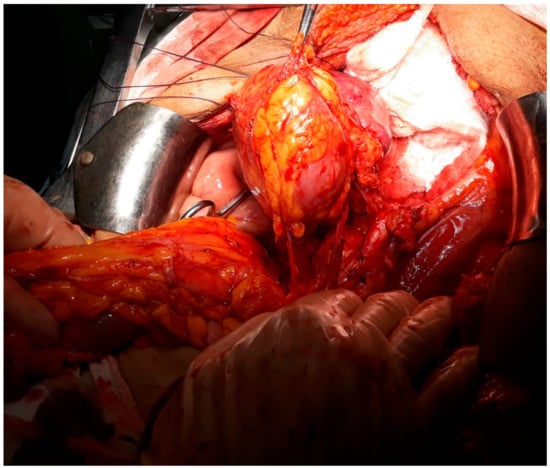

Total Exenteration En Bloc with a Nephrectomy for Locally Advanced Cervical Cancer Invading a Pelvic Kidney—A Case Report and Literature Review

2. Case Presentation